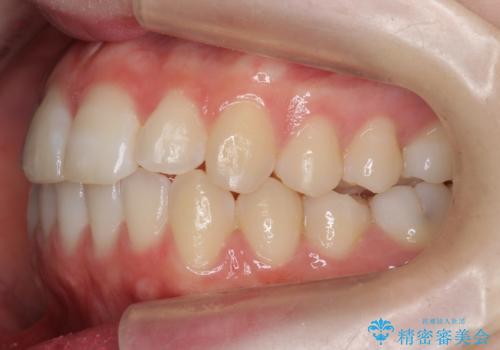

前歯のがたつき 乳歯を抜かずに矯正

- 前歯のがたつきを主訴に来院。

右上に乳歯が残っていましたが、後継永久歯がないため、抜かずに矯正しました。

乳歯の部分が反対咬合でしたが、歯列矯正で被蓋が改善するように移動させました。

右上の乳歯は移動させましたが、幸い矯正後にぐらつくこともなく、そのまま抜けるまで使うことにしました。